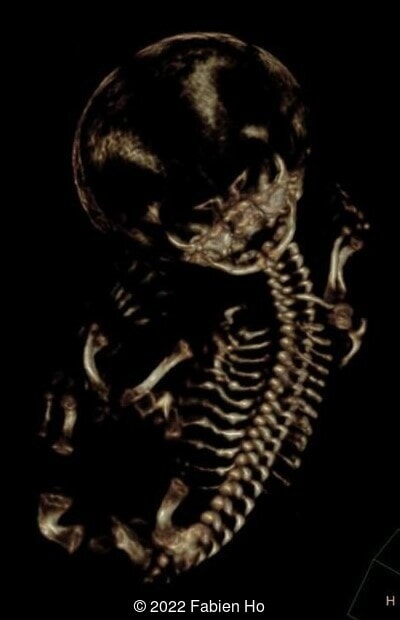

The prenatal CT scan showed:

- Low bone density of skull and lower limbs

- Moderately narrowed and bell-shaped thorax

- Numerous bone calluses of the posterior arcs of the ribs

- Normal bone density of the spine

- No platyspondyly

- Normal pelvis without iliac spine or other anomaly

- Very short long bones with curved femurs, tibias and fibulas. The curvature of the long bones reaches a 90° angle concerning for fracture. Upper limbs are moderately curved without fracture.